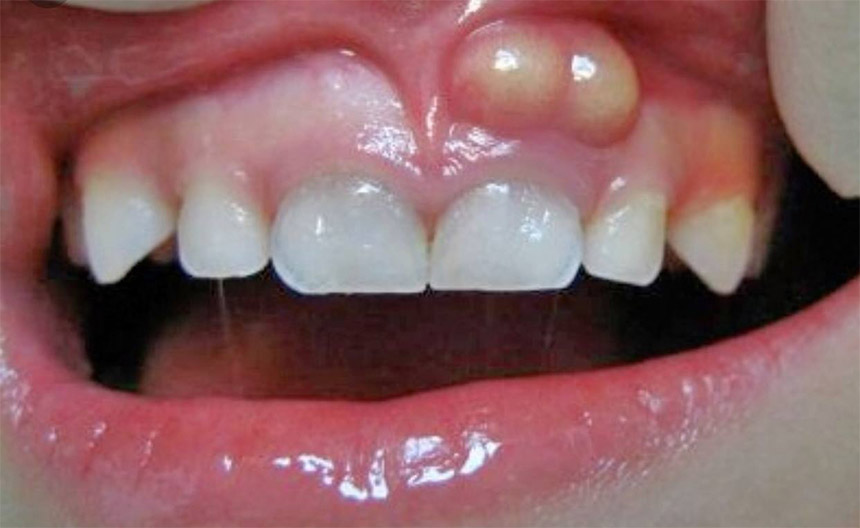

آبسه دهان

در صورت رعایت نکردن و ایجاد عفونت در لثه، ممکن است به تشکیل ورم چرکی در دهان، که آبسه نامیده میشود بیانجامد. آبسه به درمان سریع نیاز دارد. شخصی که آبسه دارد، ممکن است ورم دردناک و ترشح چرک از لثه داشته باشد. عفونتهای درمان نشده، عوارضی به همراه دارد؛ برای مثال:

بافت عفونی ممکن است ریشه دندان کناریاش را در وضعیت خطرناکی قرار دهد که در نهایت این امکان وجود دارد که آن دندان از بین برود.

علاوه بر آن، عفونت بافت ممکن است به فک یا استخوان اطراف منتقل شود و باعث آسیب به بافت شود. باکتری همچنین ممکن است وارد جریان خون شود و در سایر قسمتهای بدن مشکلی ایجاد کند.